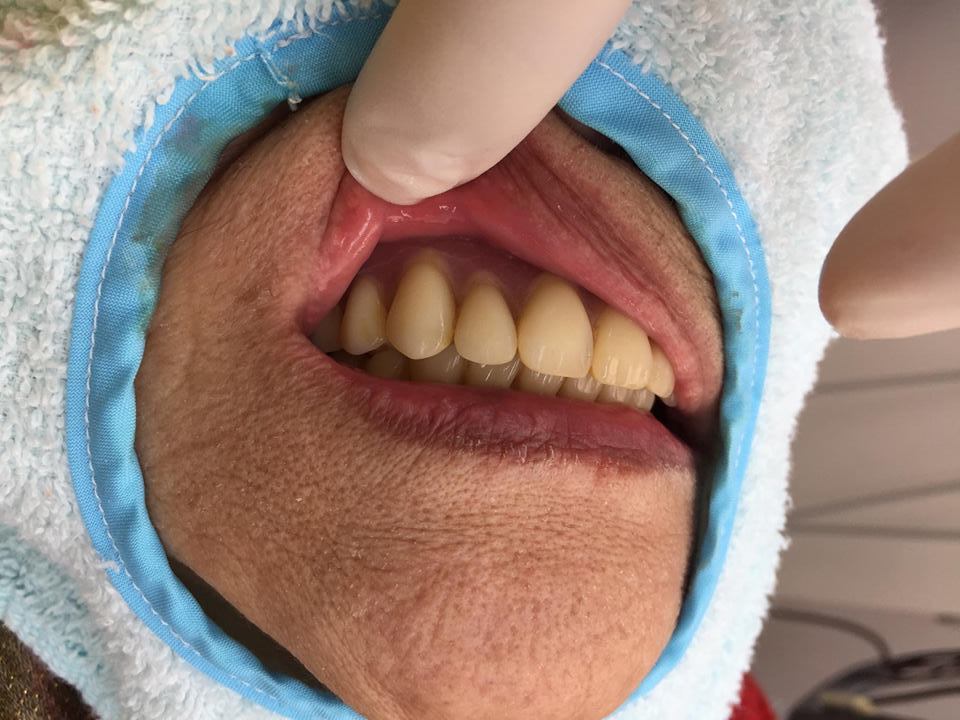

歯にクラウン(冠)としてかぶせたり

インレーとして詰めたり

義歯(入れ歯)のクラスプ(バネ)として使用する

銀色の合金。